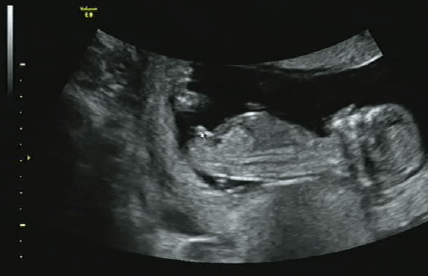

40주의 기간을 지나며 폭풍 성장하는

아기의 성장과정은 정말 신기합니다.

어느덧 얼굴 윤곽을 확인할 수 있을 정도로 성장하여

40주 만에 세상으로 나올 준비를 끝내니 말이죠.